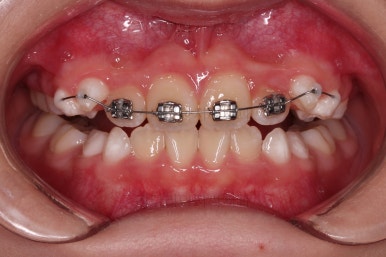

위턱뼈가 앞으로도 점점 나와서 처음 보다는 반대교합 경향이 개선되고 있는게 보이네요.

앞니도 굉장히 가지런해졌고요.

반대교합 경항도 거의 없어졌어요.

총 13개월 걸려서 부산초등학생교정 위턱의 3차원적 성장과 앞니 가지런함을 다 이뤘어요.

앞니의 반대교합 뿐만 아니라 어금니 반대교합도 개선되었네요.